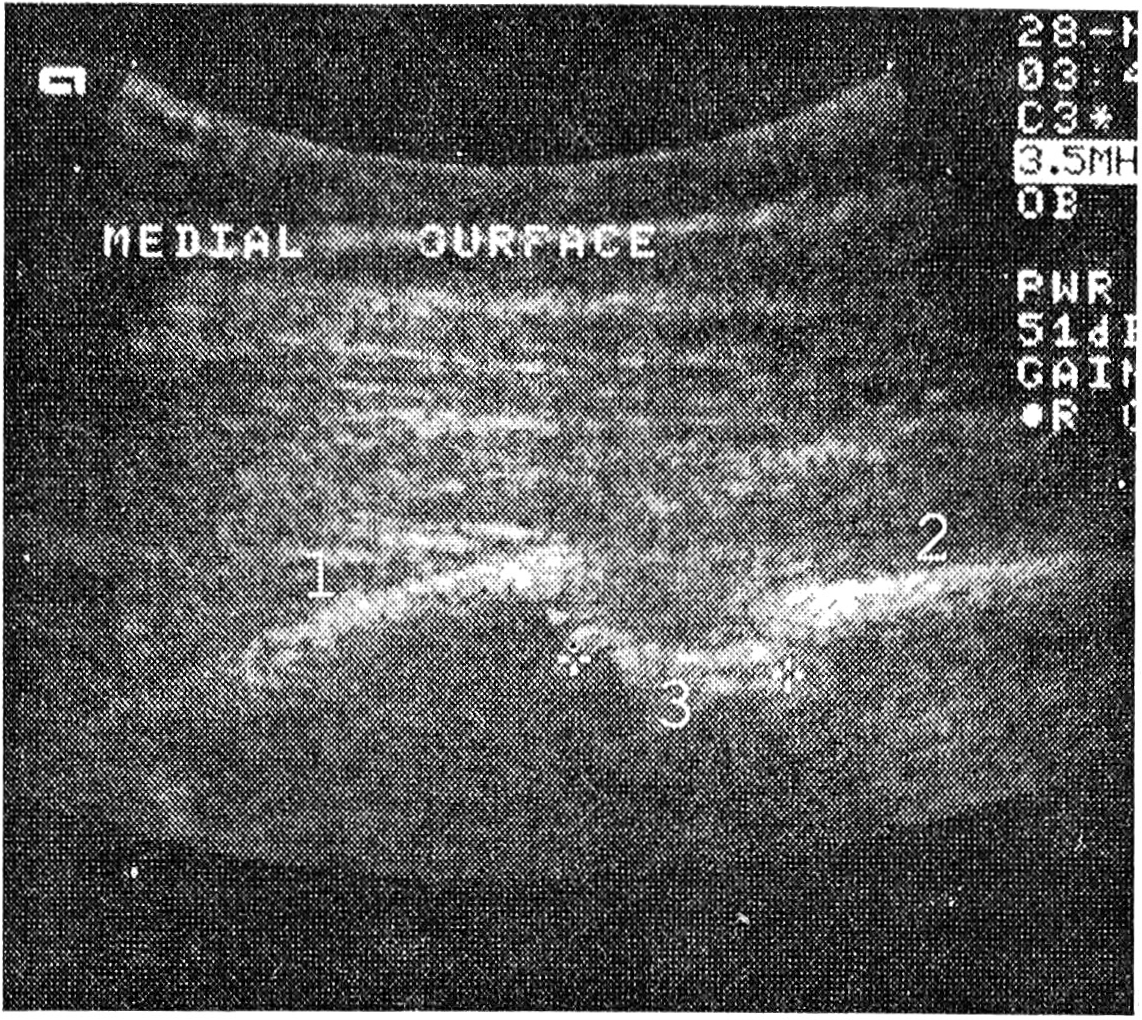

Кортикальный слой нормальной кости визуализировался в виде линейного непрерывного гиперэхогенного образования с дистальной акустической тенью, а компактная кость — исключительно при повреждении кортикального слоя. В месте перелома кости имелся перерыв гиперэхогенного сигнала кортикальной пластинки, часто имеющий ступенеобразную форму (рис. 1, 2). “Ступенька” в данном случае отражала степень смещения отломков и подвергалась количественной оценке. В проекции перелома практически всегда имели место травматические и воспалительные изменения в мягких тканях (гематома, отечность и т.д.). Благодаря возможности мультиплоскостного исследования с достаточной четкостью оценивали конфигурацию костных отломков, присутствие свободно лежащих костных фрагментов, их размеры и взаимоотношение с окружающими тканями и структурами.

Рис. 1. Сонограмма места огнестрельного перелома нижней трети правой плечевой кости. Спустя 1 месяц после травмы, замедленная консолидация перелома: 1 — эхокартина неизмененной кости; + + — дефект кости.